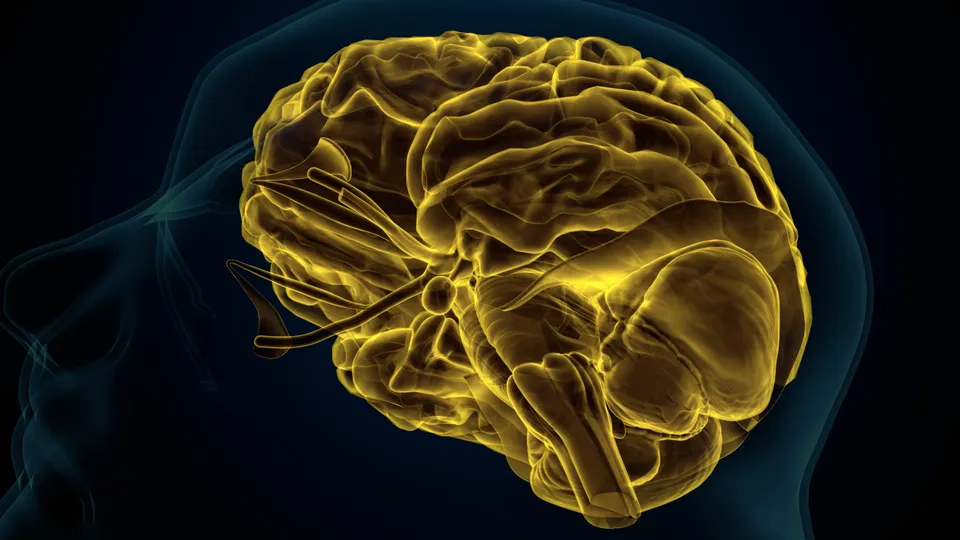

Una reciente investigación expone una conexión cada vez más relevante entre el intestino y el cerebro, destacando que la formación de recuerdos depende en gran medida de la comunicación entre ambos sistemas. El estudio señala que, con el envejecimiento, los cambios en la microbiota intestinal influyen directamente en la actividad cerebral, especialmente en regiones vinculadas a la memoria como el hipocampo, afectando la capacidad de generar nuevos recuerdos.

De acuerdo con la información, el intestino y el cerebro mantienen un diálogo constante conocido como el eje intestino-cerebro, en el que intervienen señales nerviosas, hormonales e inmunitarias. Esta comunicación se ve facilitada principalmente por el nervio vago, encargado de transmitir información interna del organismo hacia el cerebro. Sin embargo, los investigadores advierten que, con el paso del tiempo, este mecanismo de percepción interna, llamado interocepción, pierde eficacia, lo que reduce la capacidad del cerebro para responder adecuadamente a las señales provenientes del intestino.

El estudio también detalla que alteraciones en la microbiota intestinal, como el aumento de ciertas bacterias y la acumulación de sustancias inflamatorias, pueden interferir en la transmisión de señales nerviosas. Esto provoca una respuesta inflamatoria de bajo grado que afecta la comunicación neuronal y, en consecuencia, la formación de recuerdos. En este contexto, los científicos destacan que comprender esta relación abre nuevas perspectivas sobre el envejecimiento cognitivo y la importancia de mantener un equilibrio en la salud intestinal para preservar funciones cerebrales esenciales.